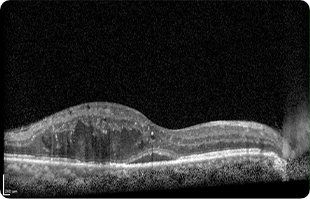

망막전막

망막전막이란?

망막 표면에 혈관이 없는 반투명한 막조직이 형성되어 황반에 기능이상을 일으키는 질환으로 막이 점차 두꺼워지고 망막이 뒤틀리면 황반부종이나 망막주름 등의 질환을 일으킬 수 있습니다.

증상

망막전막이 생기는 위치와 두께, 혼탁 정도, 막의 수축 등에 따라 다양하게 나타납니다. 대부분은 증상이 천천히 나타나지만 급격하게 나타나기도 하며 망막전막의 정도에 따라 시력저하와 상이 왜곡되어 보이는 변시증의 증상이 가장 흔하게 나타납니다.

치료

망막 전문의 수술 (유리체절제술)